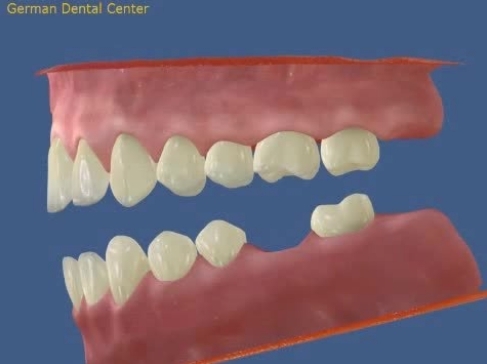

- Исправление прикуса